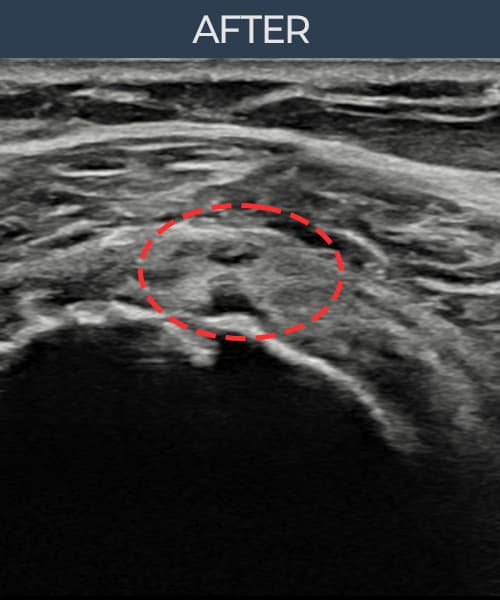

시술 전 초음파 측정 결과 파열 크기는 6mm × 3mm (힘줄 두께의 약 35% 결손)로 확인되었습니다. 시술 전 초음파에서 운동 부상으로 인한 회전근개 결손과 힘줄 내 불균질 에코 소견이 확인되었습니다. 시술 후 초음파에서 결손 부위에 섬유성 재생 조직이 형성되었으며, 힘줄 두께와 연속성이 정상 수준으로 회복된 것이 관찰되었습니다.

30대 후반 남성 환자분으로, 주 5회 웨이트 트레이닝을 즐기시는 분이었으며 운동 중 무리한 덤벨 프레스 동작에서 어깨를 다치셨습니다. 부상 후에도 운동을 지속하다 통증이 심해져 내원하셨고, 초음파 검사에서 회전근개 부분파열이 확인되었습니다. 젊은 연령대임에도 파열이 이미 진행된 상태였으며, 장기적인 운동 복귀를 위해 구조적 봉합이 필요하다고 판단하여 축소봉합술을 시행하였습니다. 시술 후 8주간 과도한 팔 사용을 제한하였고, 이후 단계적으로 재활 운동을 병행하였습니다. 4개월 후 가벼운 운동부터 재개하였으며, 최종 경과 관찰에서 힘줄 결손 부위의 완전한 재생이 확인되어 운동에 완전히 복귀하셨습니다.